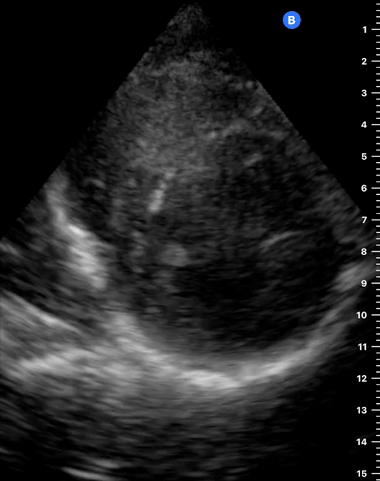

PSAX

PARASTERNAL SHORT-AXIS VIEW

As the transverse (short-axis) images show the relative wall thickness and contractility, this view is the best for assessing regional wall motion. Also, the inferior portion of the view (papillary muscles) is ideal for comparing the relative size of both ventricles. In expert hands, the superior portion of the view allows evaluation of the aortic valve and RV overload.

ORIENTATION & TECHNIQUE

A good PSAX starts from a proper parasternal long-axis. Without sliding or displacing the probe, rotate it 90º clockwise so the marking points to the left shoulder. The resulting image is a transverse cut to the heart’s long axis, hence, a short-axis view.

While maintaining the short axis, sweep or gently fan the probe along the long axis to obtain a series of ‘sectional’ views of the LV and RV.

PITFALLS

Common mistakes when acquiring a PSAX view are starting from an oblique, poorly achieved PLAX (not parallel to the long axis), leading to a 'false' short axis, and tilting the probe instead of sweeping it along the long axis, which ends up distorting the image.